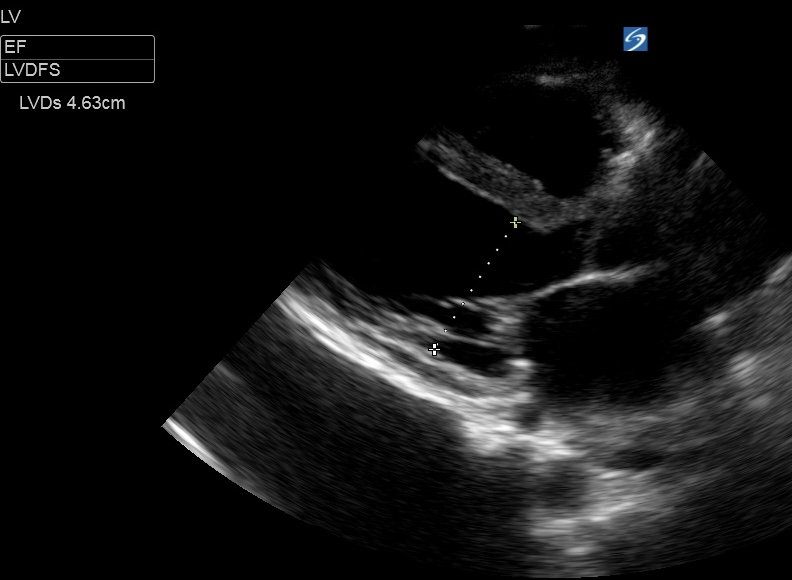

Fractional Shortening (FS):

This method measures the size of the LV base at end-diastole and end-systole, using the difference to calculate the ‘shortening’ of the LV basal diameter. FS is the difference (diastole - systole), divided by the diastolic diameter (x100 to give a %). A normal fractional shortening is around 25-45%. This can be converted to an EF using the ‘Teichholz’ method which assumes the LV is a hollow cone with a uniformly ‘shortening’ diameter (not a perfect model) and the machine will calculate this for you.

To measure the LV base you must obtain a good PLAX view and freeze the clip, before cycling through the frames to find end-diastole (called LVDd aka LVEDD - immediately as the mitral valve closes, when the LV cavity is at its largest), and measuring the LV base through a line through the tips of the mitral valve. Do the same for end-systole (LVDs aka LVESD - the frame immediately before the MV opens, when the LV cavity is at it’s smallest), this time measuring fractionally further towards the apex to allow for the systolic excursion of the mitral valve.

Tips:

• measure perpendicularly across the LV [inner edge to inner edge of the myocardium] . The benefit of this method over M-mode is that you can measure more vertically-orientated hearts in which it is often impossible to get the M-mode cursor to track across the LV base faithfully.

• watch several cardiac cycles to get an idea of where the LV walls reach during systole to make an accurate measurement of LVDs

• This method also gives you an objective LV size, and allows diagnosis of LV dilation (a normal LVDd is generally < 5.5cm but there are differing ranges for men and women, and it is usually indexed to BSA)

This patient had a LVDd of 5.16cm and LVDs of 4.63cm

Fractional Shortening was ((5.16-4.63)/5.16) x 100 = 10%.

This is severe LV impairment.